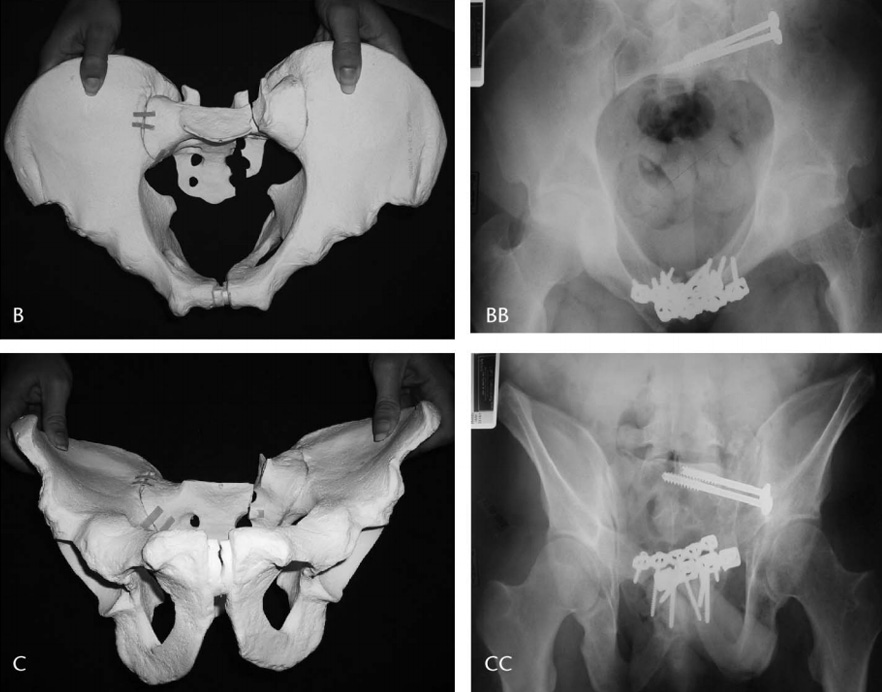

Table Skeletal Fixation in Pelvic Ring Reduction

In this article, Dr. Joel Matta and Dr. Jonathan Yerasimides evaluate the use a pelvic frame as a means of external skeletal fixation in fracture cases.

In this article, Dr. Joel Matta and Dr. Jonathan Yerasimides evaluate the use a pelvic frame as a means of external skeletal fixation in fracture cases.